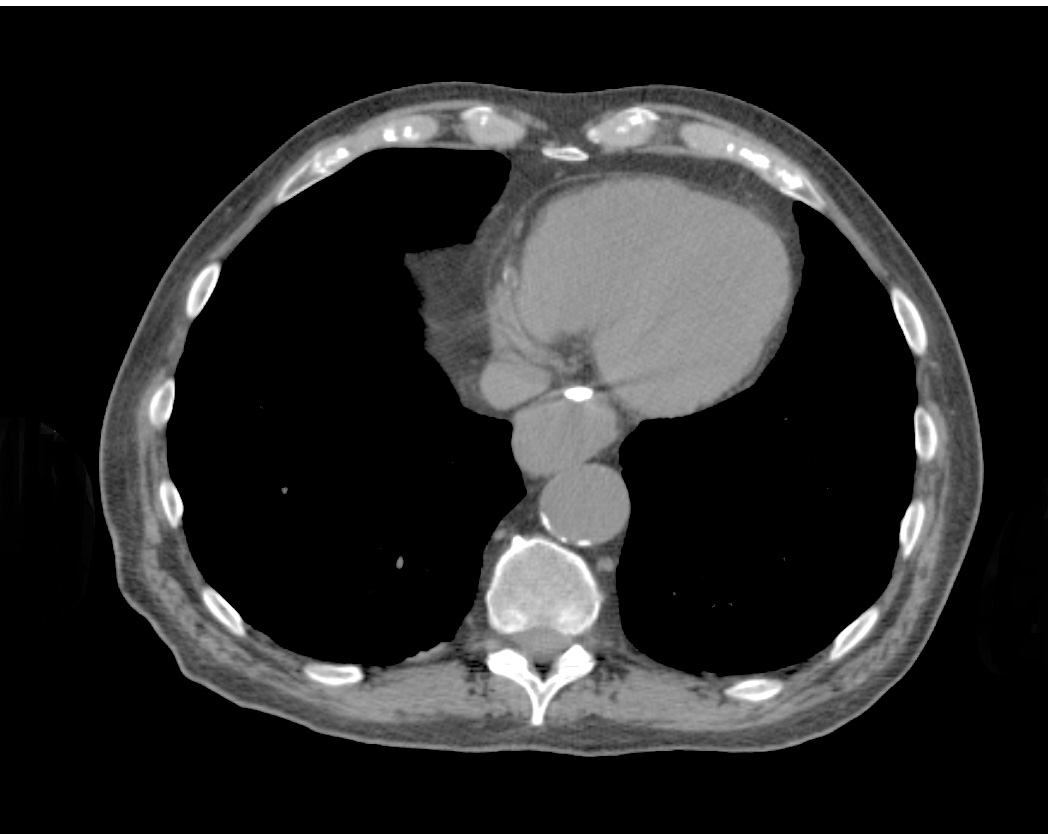

BioXmark® (1mL) is indicated for use to radiographically mark soft tissue in or adjacent to malignant tissue in the thoracic region during a surgical procedure for at least two months after placement. BioXmark® is injected via very thin needles (endoscopically or percutaneously) and provides visibility of the target throughout the treatment. It is biodegradable and is completely resorbed within a few years.

BioXmark® is visible on x-ray, CT, CBCT, fluoroscopy, MRI and ultrasonography enabling multi-modality image-guided planning and treatment, which is becoming the standard treatment approach in radiotherapy in hospitals across Europe. Compared to conventional metal based soft tissue markers, BioXmark® creates limited artefacts in CT and MRI and induces minimal dose perturbation in proton therapy. Moreover, BioXmark® has no sharp edges, which tend to cause migration of conventional metal based markers in patients.

"We have tested BioXmark® in patients with lung cancer and found that it is easy to work with and clearly visible. Markers were injected in tumour tissue, lymph nodes and lung tissue and we observed no migration from the planning CT to end of treatment ,” said Lena Specht, MD, PhD, Professor of Oncology, Dept. of Oncology, Rigshospitalet, Copenhagen University Hospital, Denmark. “ We have also tested BioXmark® in patients with oesophageal cancer and saw no migration between planning CT to end of treatment, and again, BioXmark® was well tolerated."